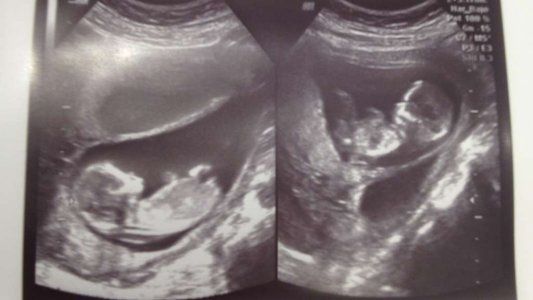

Se ha viralizado un video increíble que muestra la lucha de dos hermanitos en el útero de la madre. El hecho sucedió en China cuando la mujer se estaba realizando una ecografía de rutina.

Cuando comienzan el trabajo se aprecia como los dos bebés estaban peleándose. El padre agarró su teléfono celular y comenzó a grabar la escena que se ha hecho viral.